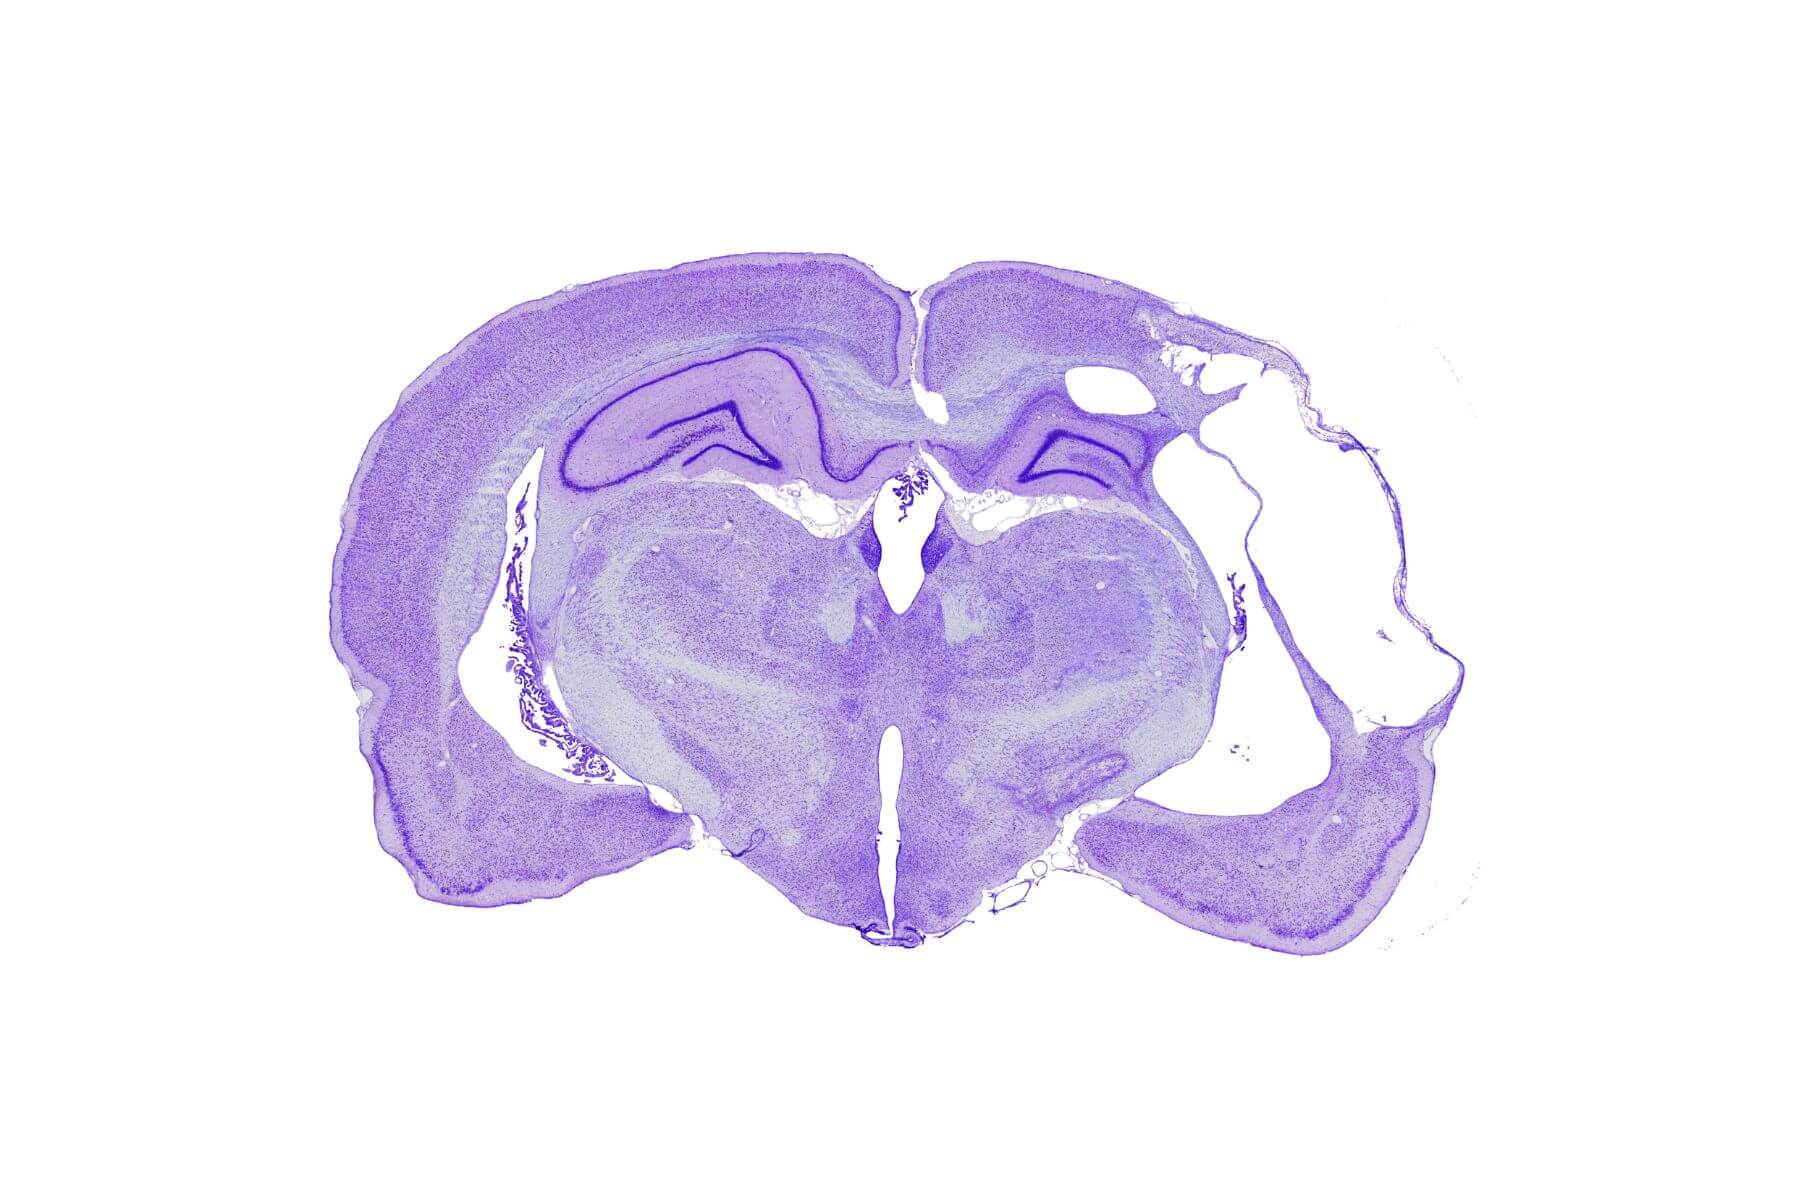

Immunohistochimie, immunofluorescence et histologie

STROK@LLIANCE réalise pour vous des études de pharmacologie préclinique dédiées aux maladies neurovasculaires et aux pathologies du CNS. Nous proposons une gamme complète de services, de la cellule au gros animal, avec des études standards ou sur-mesure : POC, PK/PD, safety non BPL, identification et suivi de biomarqueurs. Nous répondons à vos besoins en évaluation préclinique dans le domaine des pathologies neurovasculaires et de l’hémostase. Nous avons quatre domaines d’expertise dans l’AVC et les atteintes aigues du système nerveux central : le criblage in vitro sur sang humain, l’AVC ischémique, l’AVC hémorragique et l’évaluation des risques de saignement associés aux traitements.